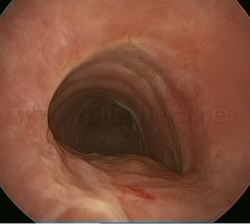

Estenosis

traqueal |